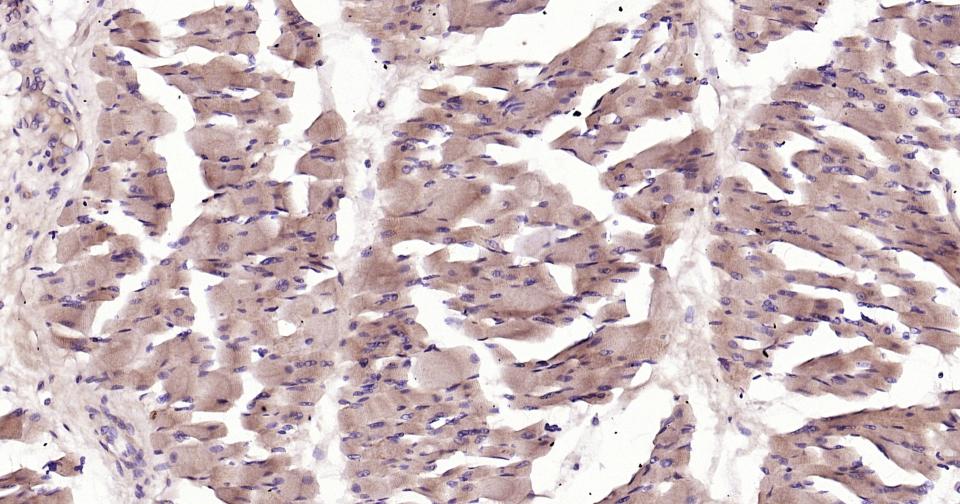

Tissue/cell: mouse heart tissue; 4% Paraformaldehyde-fixed and paraffin-embedded; Antigen retrieval: citrate buffer ( 0.01M, pH 6.0 ), Boiling bathing for 15min; Block endogenous peroxidase by 3% Hydrogen peroxide for 30min; Blocking buffer (normal goat serum,C-0005) at 37℃ for 20 min; Incubation: Anti-Glut12 Polyclonal Antibody, Unconjugated(bs-2540R) 1:200, overnight at 4°C, followed by conjugation to the secondary antibody(SP-0023) and DAB(C-0010) staining